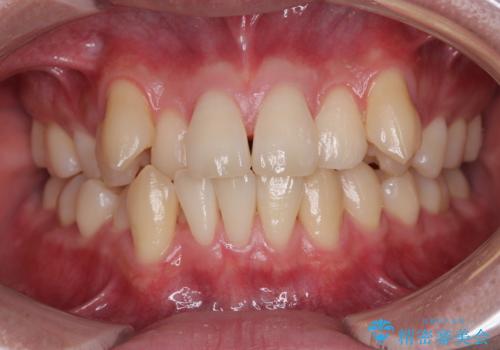

【モニター】八重歯と前歯のクロスバイト ワイヤーを併用しインビザラインで矯正治療

- 前歯のデコボコと八重歯を気にして来院された患者様です。

インビザラインでの治療を希望されていましたが、前歯のクロスバイトや下顎小臼歯の捻転が認められたため、インビザライン単独で治療を行うよりも、ワイヤー装置を併用した方が、治療期間の短縮やトラブル回避できると判断し、ワイヤー装置を併用することとしました。

まずはワイヤー装置により前歯のクロスバイトと下顎小臼歯の捻転を改善し、その後インビザラインにより全体を整える矯正治療を行うこととしました。